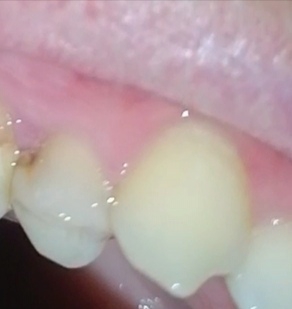

1000070960.jpg

1000070961.jpg

Зуб пятерка. Возможно такое вылечить, анонче? Отклолся как то, вообще не болит.